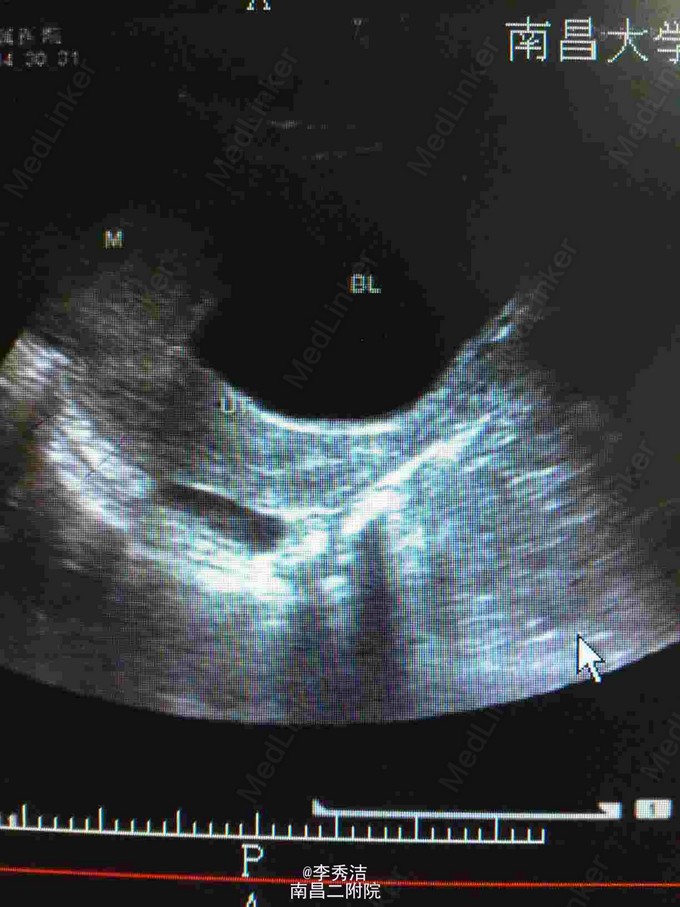

查体:中下腹部明显彭隆,未见肠型及蠕动波,未见腹壁静脉曲张,腹肌软,下腹部可触及约20*20cm包块,质硬,活动度差,叩诊实音,肝脾肋下未及,妇科检查:外阴:已婚未产式;阴道:畅软,少量白色分泌物;宫颈:少糜,宫体及双附件因盆腔巨大包块扪诊不清。血清HCG70.1mIU/ml。腹部CT示腹盆腔内见一巨大包块影,大小约16*8.1cm,增强扫描示不均匀增强,腹腔、盆腔内见积液,结合血清HCG,不排外生殖系统恶性肿瘤可能。彩超示:子宫上方巨大包块,不排除来源于附件可能,子宫、显示不清。双侧附件